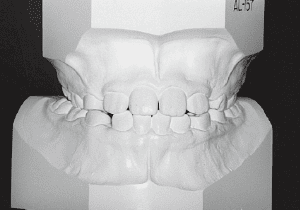

2 After treatment 2-10-’99

The Edgewise appliance was applied locally (8) and removed after 11 months (9). However, as the maxillary molar region gradually became crossbite, the maxillary arch was laterally expanded using a quad helix.